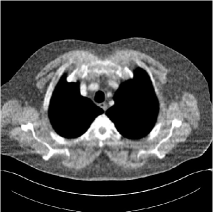

Fig. 3: Three examples (from top to bottom) of the reconstructed testing images using Momentum-Net with SimpleCNN (the second column), with SimpleCNN-RSN (the third column), and with Dn-RSN (the fourth column). The compared WavResNet denoised images are shown in the first column, and the reference images are in the fifth column. See their FBP images in Fig. 4.

Refer to caption

Fig. 4: FBP images of test examples.

3.2 Proposed Momentum-Net with SimpleCNN

Fig. 2 shows that the proposed Momentum-Net with SimpleCNN decreases RMSE dramatically in the first 30 layers, and tends to converge in 50 layers. The Momentum-Net reduces the mean RMSE value by 4.5 HU and gives smaller standard deviations in RMSE, compared to WavResNet, as reported in Table 1. This implies that the proposed Momentum-Net with SimpleCNN can improve both the accuracy and stability of low-dose CT image reconstruction than a state-of-the-art image denoising deep NN, WavResNet. The proposed Momentum-Net with SimpleCNN better removes noise and streak artifacts than WavResNet. It also provides clearer reconstructions of some details; see, in Fig. 3, the boundaries shown in the zoomed region at the top-right corner in the first example, the arrow pointed structures in zoomed areas of the second example, and the arrow pointed tissues in the left zoomed region in the third example.

3.3 Momentum-Nets involving RSN-based training

We show the reconstructed examples by Momentum-Net with SimpleCNN-RSN and Dn-RSN in the third and fourth columns of Fig. 3 respectively. Comparing the first three and the last columns in Fig. 3, we observe that Momentum-Net with SimpleCNN-RSN provides generally noisier reconstructions than WavResNet and Momentum-Net with SimpleCNN. However, Momentum-Net with SimpleCNN-RSN sometimes can provide clearer details than WavResNet. For example, in the right zoomed box of the second example, Momentum-Net with SimpleCNN-RSN shows better reconstruction quality for the arrow pointed structures than WavResNet, and in the left zoomed box in the third row, the former gives clearer small tissues marked by red arrows than the latter. Table 1 reports that Momentum-Net with SimpleCNN-RSN is approximately 2.9 RMSE (HU) higher than WavResNet, while it has smaller standard deviations. This implies that Momentum-Net with SimpleCNN-RSN is more stable than WavResNet, although it may not provide better image qualities. Momentum-Net with Dn-RSN, however, provides the worst visual and numerical results among the compared four methods in this paper.